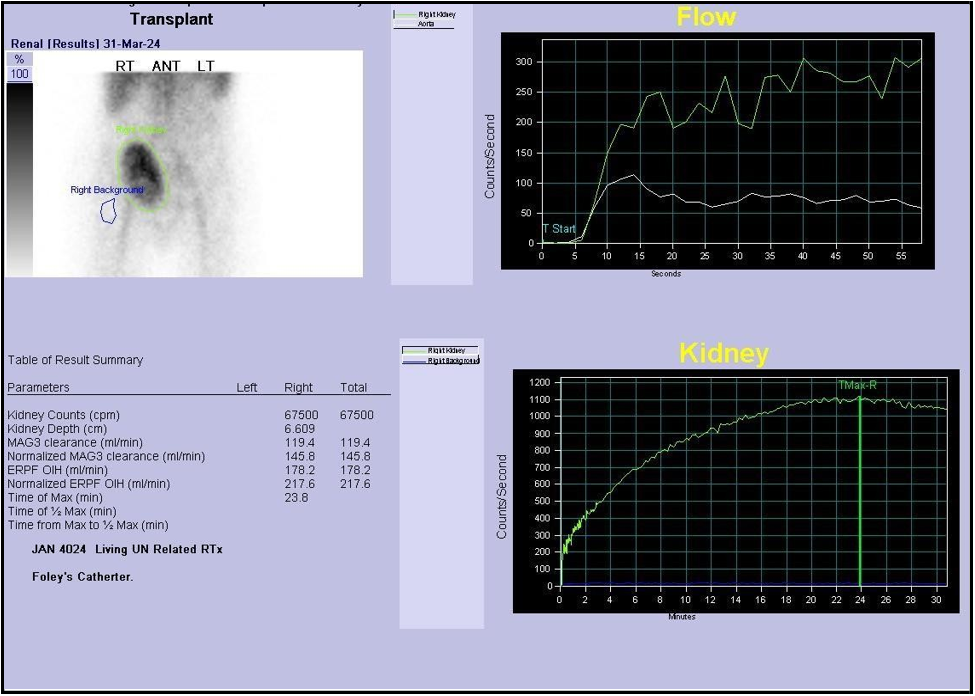

A Tc-99m MAG3 renogram was performed to further assess graft function. The scan was abnormal, demonstrating slightly reduced perfusion and progressive parenchymal retention, consistent with graft dysfunction. Differential considerations included acute rejection, vasomotor instability, and drug-induced nephrotoxicity, warranting tissue sampling and close follow-up. The observed hydronephrosis was dilated but nonobstructive, likely attributable to recent stent removal and transient urodynamic changes [Figure 5].

Figure 5: Tc-GGm renogram showing reduced perfusion with progressive parenchymal retention and dilated, non-obstructive hydronephrosis.